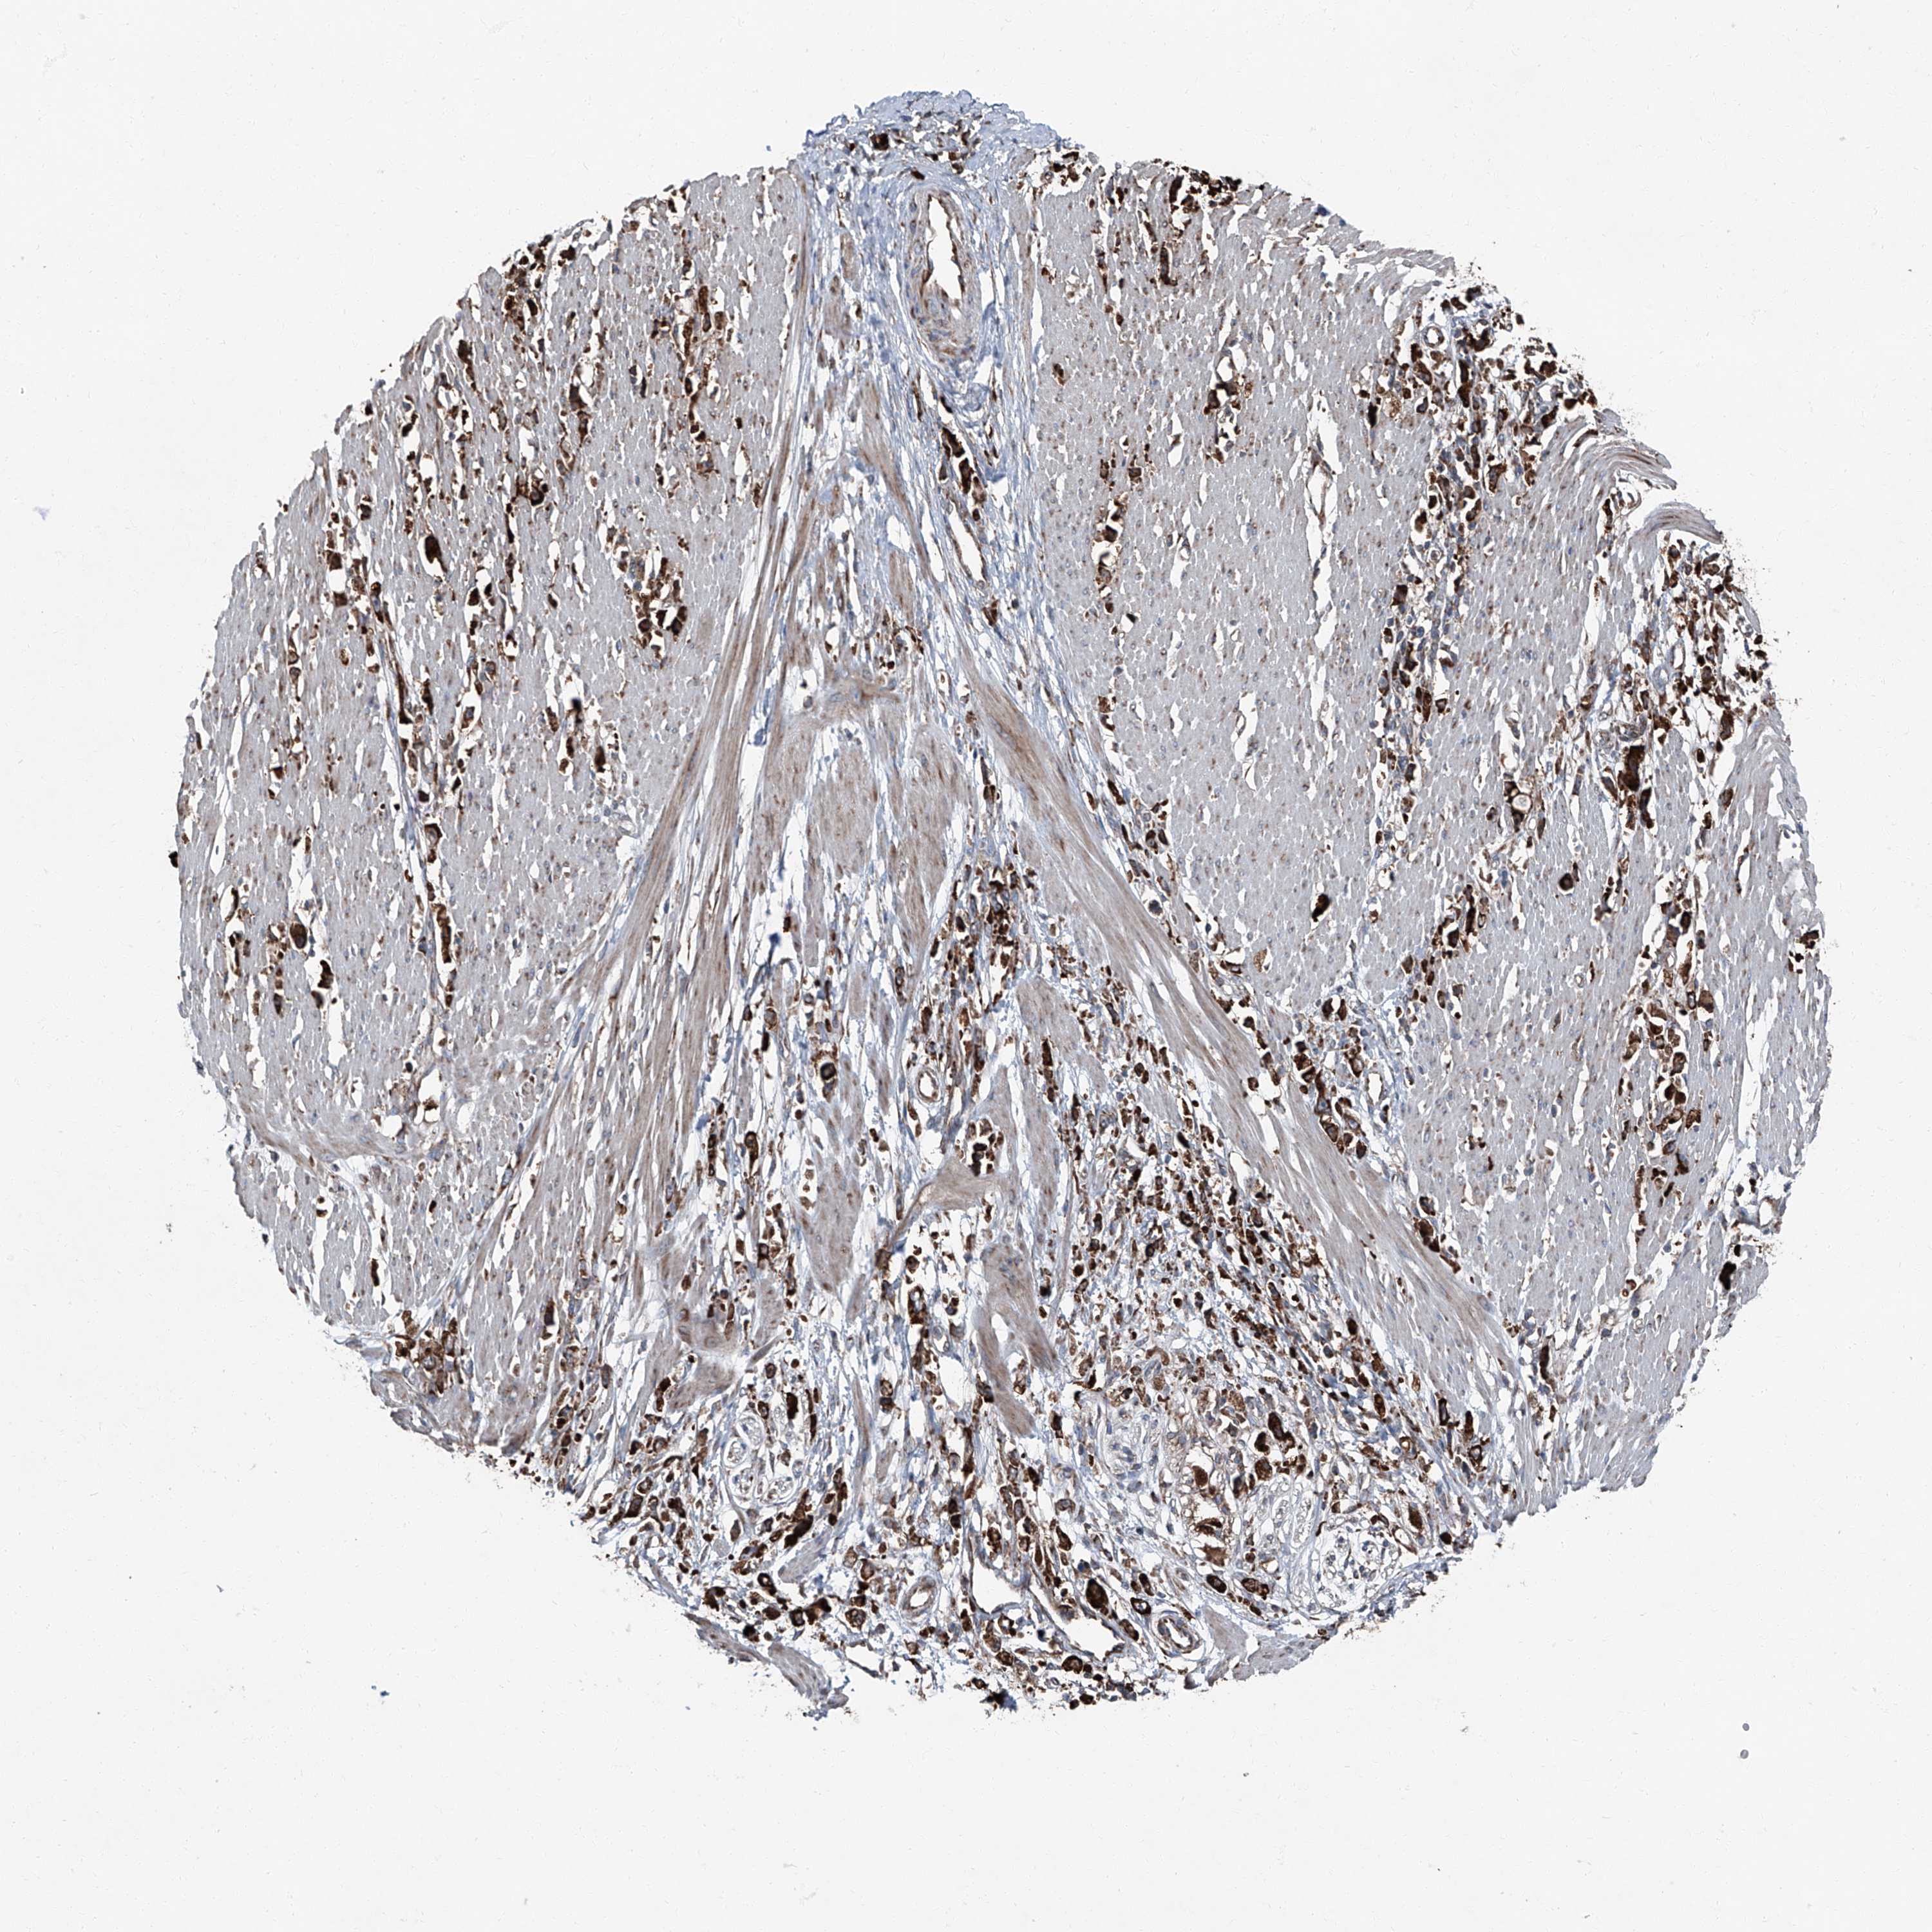

STOMACH CANCER - Protein expressioni

A mouse-over function shows sample information and annotation data. Click on an image to view it in a full screen mode. Samples can be filtered based on level of antibody staining by selecting one or several of the following categories: high, medium, low and not detected. The assay and annotation is described here.

Antibody stainingi

Antibody staining in the annotated cell types in the current human tissue is reported as not detected, low, medium, or high, based on conventional immunohistochemistry profiling in selected tissues. This score is based on the combination of the staining intensity and fraction of stained cells.

Each image is clickable and will lead to virtual microscopy that enables deeper exploration of all samples and also displays staining intensity scores, fraction scores and subcellular localization as well as patient and tissue information for each sample.

Antibody HPA028516

Antibody HPA073571

Staining

High

Medium

Low

Not detected

Intensity

Strong

Moderate

Weak

Negative

Quantity

>75%

75%-25%

<25%

None

Location

Nuclear

Cytoplasmic/membranous

Cytoplasmic/membranous,nuclear

Adenocarcinoma, NOS

Adenocarcinoma, High grade